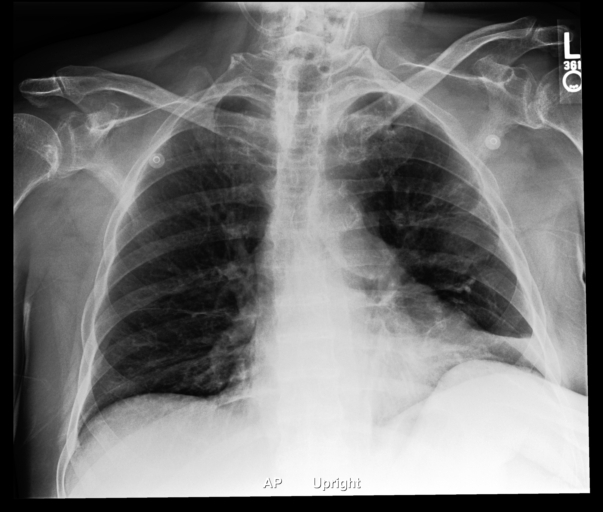

Probs: 0.146, 0.049, 0.670, 0.901, 0.616

Report:

Mild to moderate cardiomegaly is present.

There is mild perihilar vascular congestion…

There is no focal lung consolidation.

There is no pneumothorax.

There is no large pleural effusion.